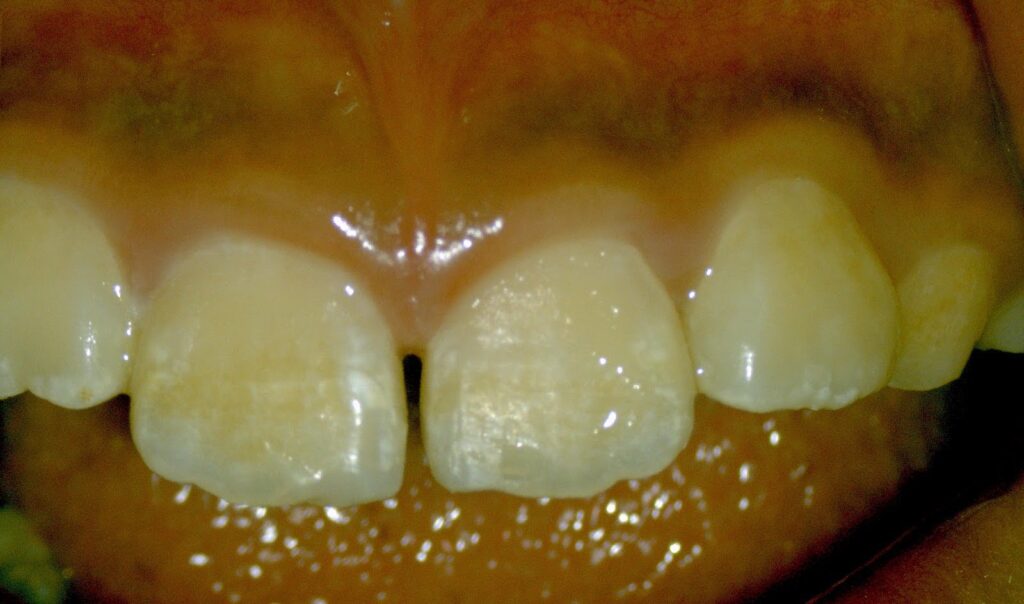

13歳~成人の方の場合

症例)

①体育の授業中に同級生とぶつかり前のめりに転倒し床に前歯強打

②幅広のパンツに足が引っかかり前へ転倒

③室内で立ちくらみ、机に前歯をぶつける

④電車内で立ちくらみの為手すりに前歯をぶつける

Dr.:歯の神経(歯髄)は、強打の為断絶してしまい、助かりません。かといって抜歯はしません。壊死してしまった根管内の歯髄を綺麗にする根管治療をします。